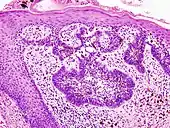

Ductal carcinoma in situ (DCIS) in breast tissue, cell nuclei (blue-purple), extracellular material (pink).

Basal cell carcinoma of the skin, cell nuclei (blue-purple), extracellular material (pink).